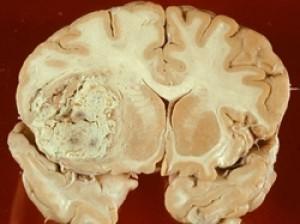

- Глиобластомой. Данное новообразование является самым опасным. Оно "прорастает" в мозговые ткани, в результате чего возникает некроз мозга. Как правило, такой недуг встречается среди людей преклонного возраста.

Астроцитомой называется опасное онкологическое заболевание, которое поражает ЦНС. Чаще всего от этого недуга страдает кора больших полушарий. Он может развиться в любом возрасте, в том числе в детском. Болезнь поражает мозжечок или основание головного мозга. В редких случаях новообразование оказывает деструктивное воздействие на спинной мозг. Опасность этой опухоли в том, что на ранних стадиях ее определить крайне сложно. Даже после проведения обследования не всегда можно поставить правильный диагноз. Это связано с тем, что по плотности опухоль практически ничем не отличается от вещества головного мозга. Внутри новообразования может образоваться киста. Она увеличивается постепенно, но может достигнуть огромных размеров. Как правило, кисты образовываются в детском возрасте.